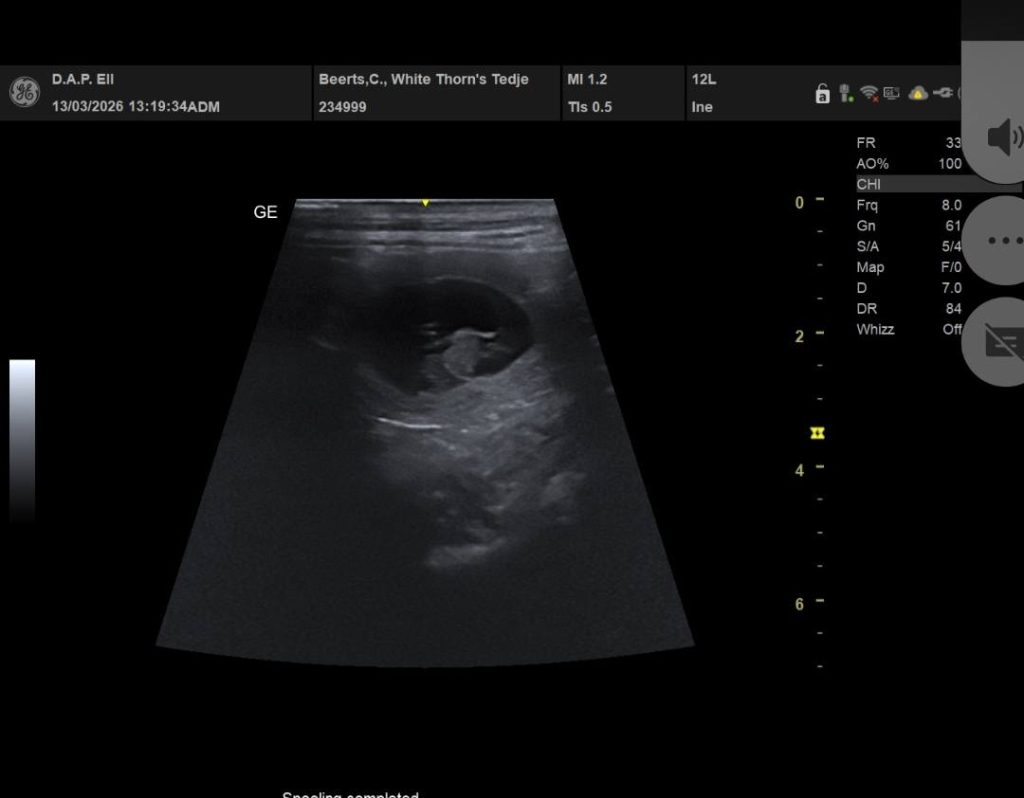

DE pups van Tedje en Moos worden rond 18 April verwacht.